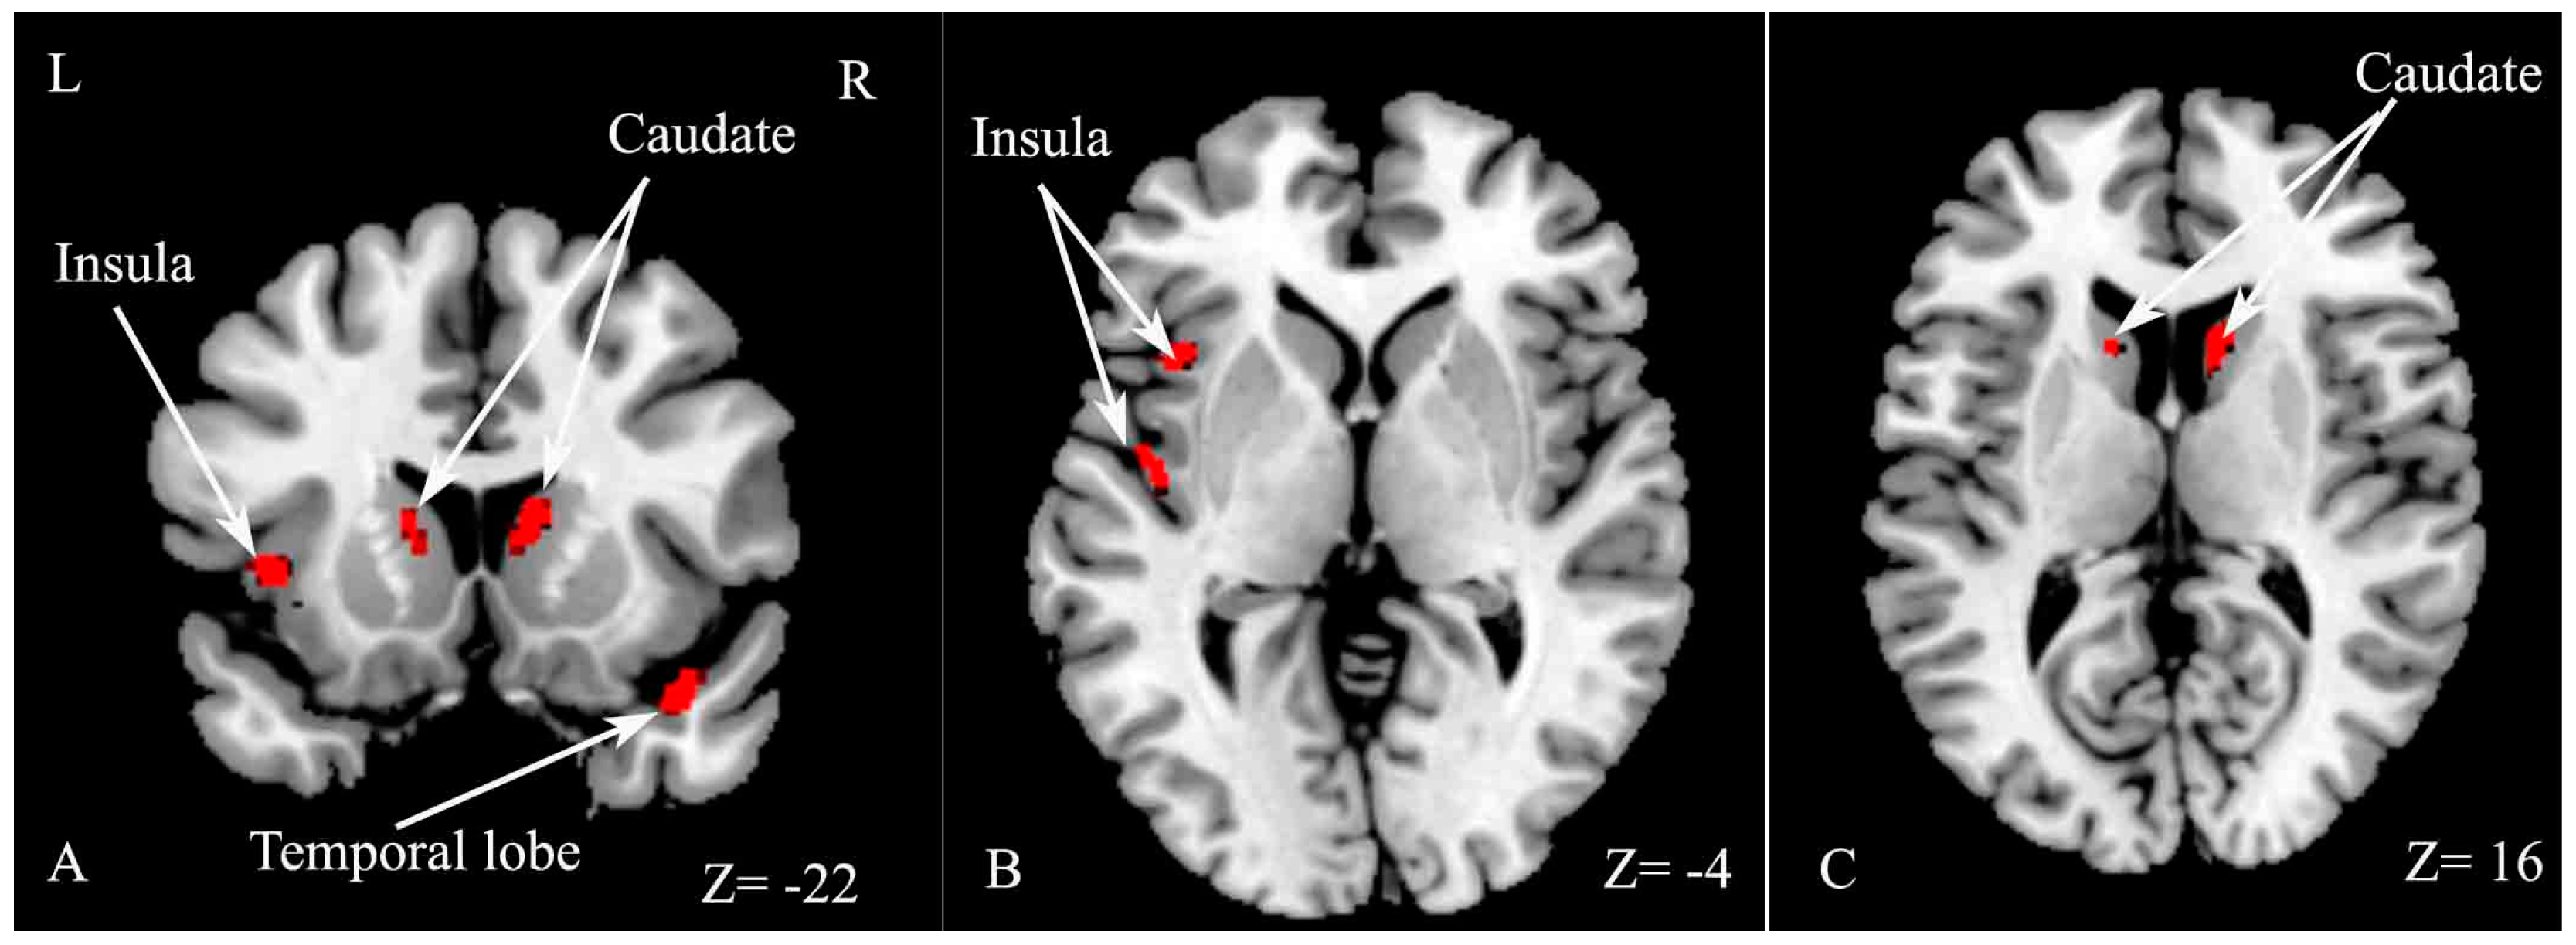

The VBM analysis indicated that GM volume significantly decreased in several regions, including the right temporal lobe, left insula and bilateral caudate in the CI group compared with the CP group (Table 4 and Figure 4).

Figure 4.

Statistical parametric mapping (SPM) regions exhibiting decreased gray matter (GM) volume in CI patients compared with CP patients (p < 0.05, FWE corrected for multiple comparisons). SPM regions exhibiting significant GM loss including right temporal lobe, left insula and bilateral caudate (A); left insula (B); bilateral caudate (C).

However, no significant difference in GM volume was found between CI and CP patients in Hulst’s study, and the authors proposed that GM was not related to cognitive deficits in MS [10]. The current results revealed significant decreased GM volume, including in the right temporal lobe, left insula and bilateral caudate nucleus in CI patients compared with CP patients. The caudate nucleus has been found to be related to verbal fluency, language learning and memory [25], and the temporal lobe is implicated in memory function and information processing speed [12,24,26]. The current results indicate that atrophy of the right temporal pole, left insula and bilateral caudate nucleus may be related to CI in RRMS. The discrepancy may be related to the different disease subtypes of MS patients between the two studies.